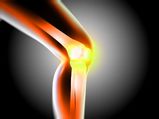

Bone Health

7 Foods To Eat For Healthy Bones

7 Foods To Eat For Healthy Bones -

10 Foods Men Need For Bone Density

10 Foods Men Need For Bone Density